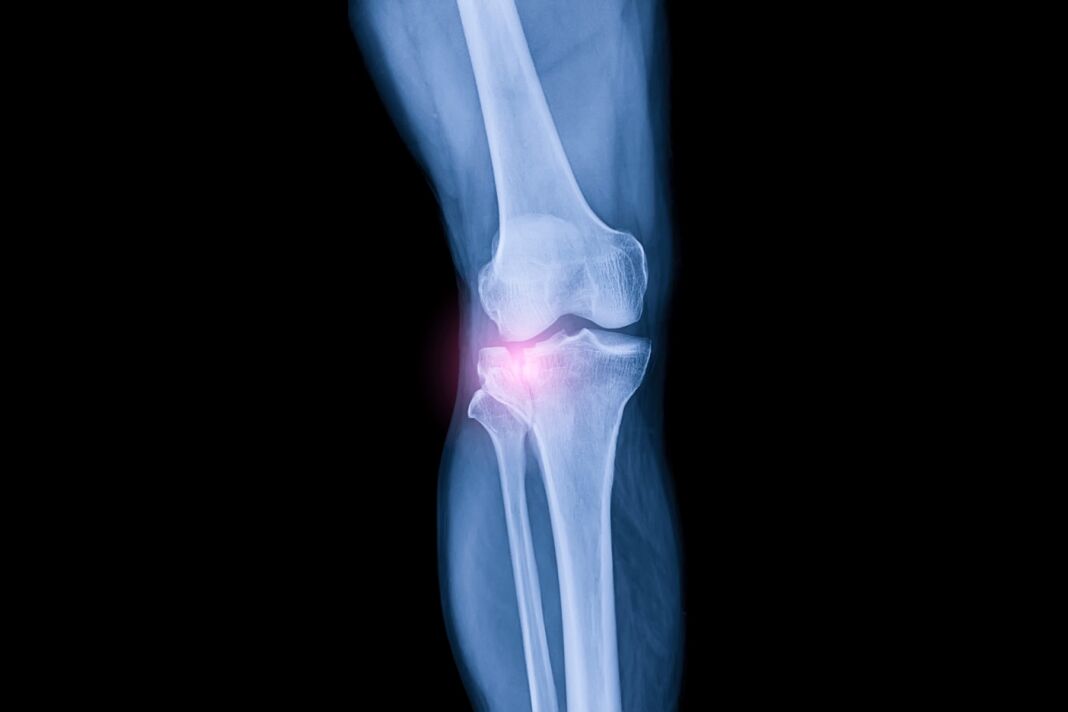

Este o tehnică imagistică avansată, non‑invazivă și versatilă, bazată pe ultrasunete. Spre deosebire de radiografia convenţională, care evidențiază în principal structurile osoase, ecografia permite vizualizarea clară a ţesuturilor moi, fiind recomandată ca investigație de primă linie în numeroase cazuri clinice.

Rolul ecografiei în diagnosticarea leziunilor de ligament

Ligamentele stabilizează articulaţiile prin legarea oaselor între ele. Leziunea unui ligament, cunoscută ca entorsă, este frecventă în sporturi. Ecografia oferă:

- Evaluarea integrităţii ligamentelor şi stadializarea gravităţii entorsei.

- Evaluare dinamică – medicul poate aplica un stres blând asupra articulaţiei pentru a observa eventuale deschideri anormale şi instabilitate articulară.